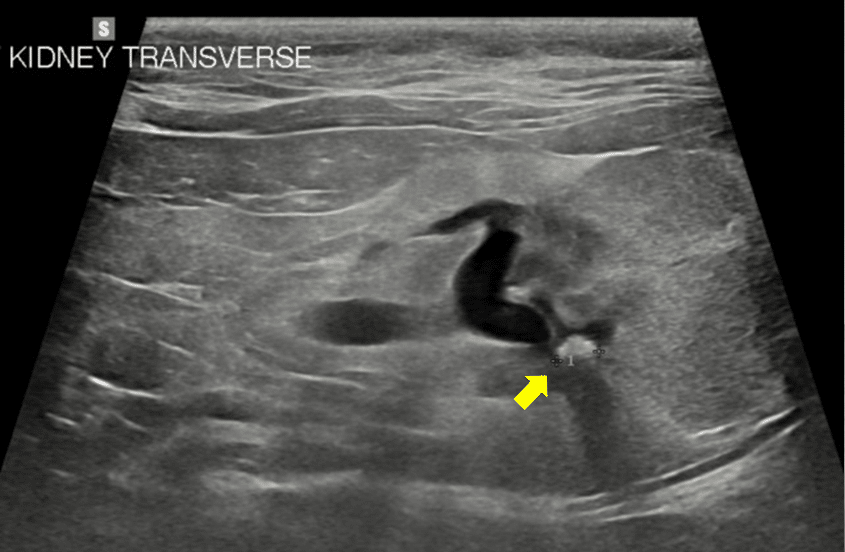

33 Top Photos Kidney Stones In Cats Ureter Urinary Calculi Stones